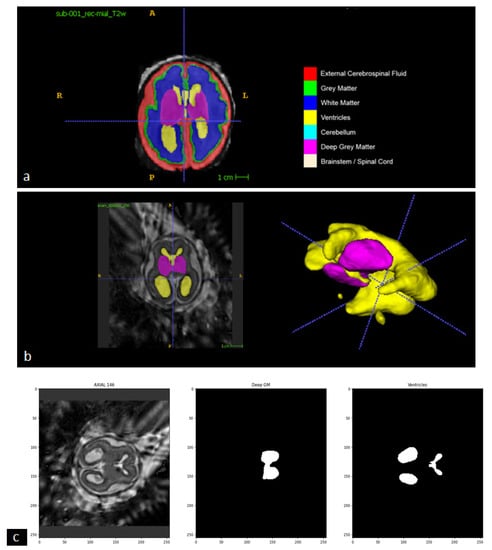

In this step of our study, we implemented the AI model adopted by the winning team of the FeTA 2021 challenge (Team name NVAUTO) to perform automatic fetal brain tissue segmentation. The AI model is based on the MONAI ResSegNet with OCR modules. The reconstructed 3D brain volume is segmented into seven tissue categories (External Cerebrospinal Fluid, Grey Matter, White Matter, Ventricles, Cerebellum, Deep Grey Matter, and Brainstem/Spinal Cord). A summary of the original model (NVAUTO) and the model adapted to our implementation (RUSH) is described in Table 1. After its assembly, the deep learning network was trained with the collection of annotated fetal MR data from the FeTA 2022 challenge.

2.5. Defining the Maximum of “Deep Gray Matter”, as a Clue for Finding the Best Slice for Measuring Ventricle

Following the automatic segmentation, the axial slice with the largest segmented area of Deep Gray Matter from the high-resolution 3D MR data is selected as the reference slice from which the width of ventricles will be measured (Figure 5) because the thalamus is included in the DGM category in the brain segmentation of the model. This is consistent with the protocol of manual measurement performed by physicians (Supplement Figure S1).

Figure 5. Key Steps in Automatic Linear Measurement of the Lateral Ventricle. (a) General Picture of the Online Dataset: The online dataset is divided into seven different tissues for analysis. (b) Utilizing Deep Gray Matter for Ventricle Identification: The Deep Gray Matter (purple segment) is used as a reference to locate and identify the ventricle (yellow segment) in the 3D version. (c) Defining Deep Gray Matter as a Clue for Ventricle Measurement: The Deep Gray Matter, specifically the Thalamus, serves as a crucial clue in selecting the optimal cut for accurate ventricle measurement. The image includes a 3D reconstructed image slice (left side), the Deep Gray Matter (middle), and the extracted ventricle (right side).